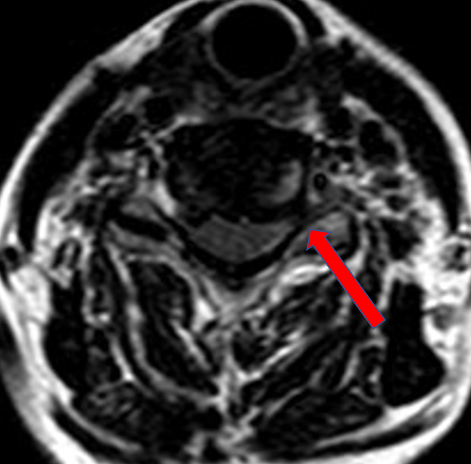

完善MRI检查后发现,颈5/6椎间盘向左外侧突出,神经根出口狭窄。徐杰教授带领团队查房详细了解患者病情和诉求后,认为其符合微创手术的适应症,可以避免开放融合手术,决定为其实施天玑机器人导航辅助显微镜通道下颈椎后路Key-hole手术。

术中精确定位后建立通道,显微镜下磨钻精准磨除椎板上下缘,显露并去除黄韧带和产生压迫的髓核组织,手术过程顺利,全程可视,脊髓零侵袭,神经根减压充分。